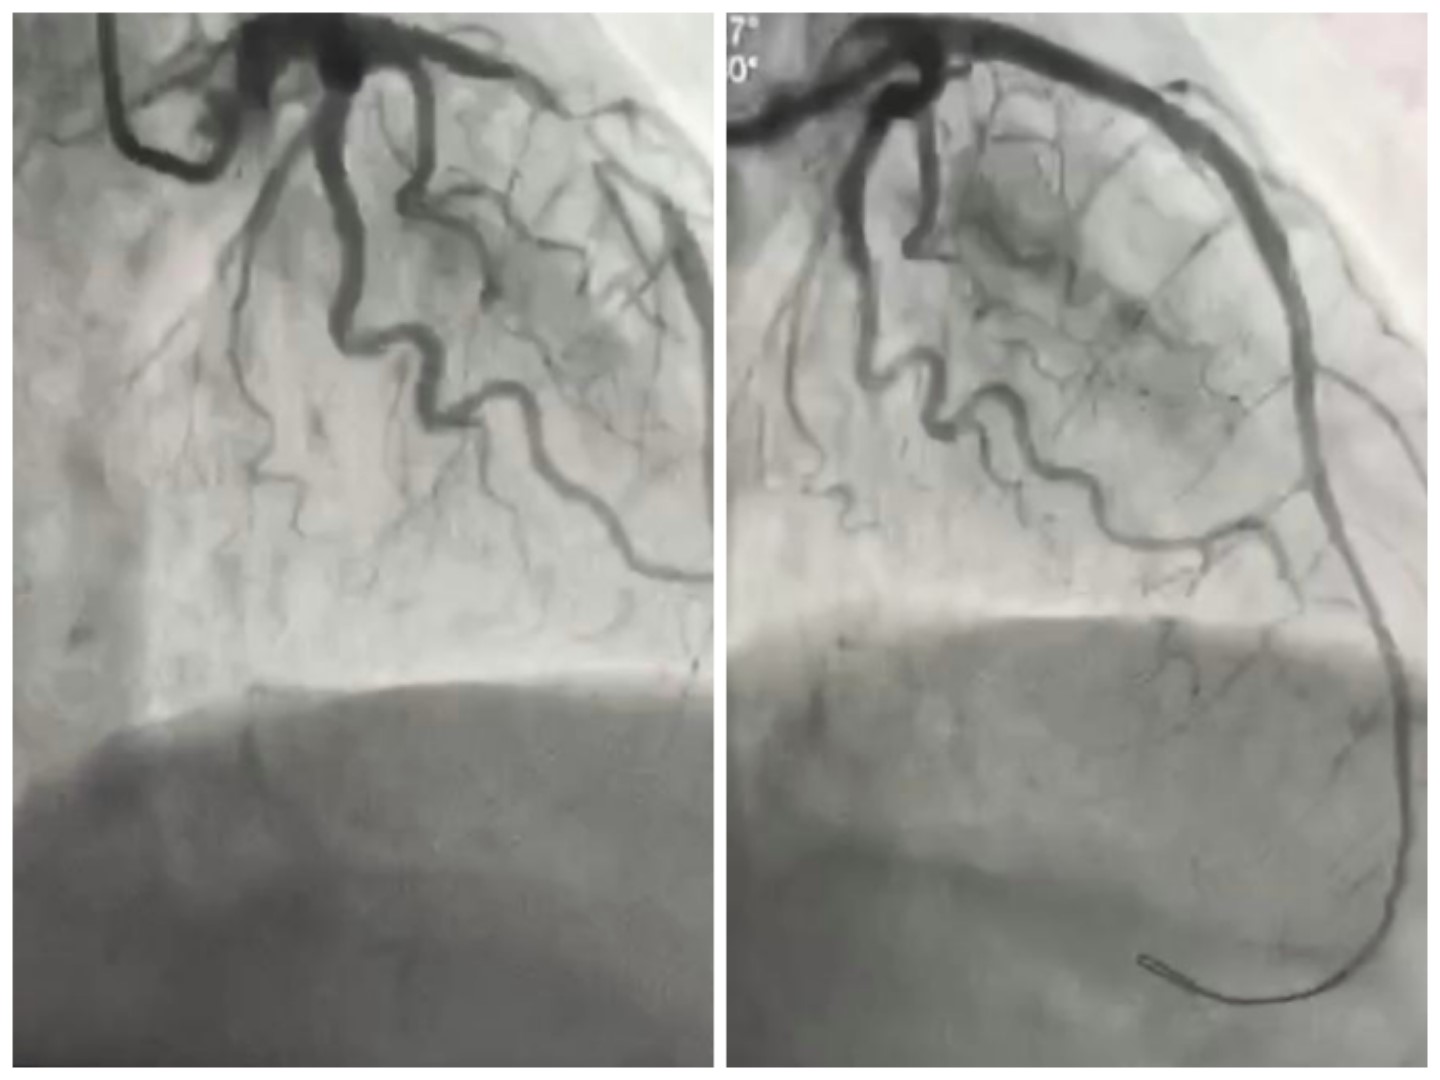

李某,女性,69岁,患者因阵发性胸痛27小时,病情加重1小时到开鲁县东风镇中心卫生院就诊,值班医生李勇为患者进行了相关检查,心电图提示为急性前壁心肌梗死。李医生第一时间将心电图等相关资料上传至胸痛联盟微信群中,经我院心内三科郑凯医生会诊,考虑为急性前壁心肌梗死,并给与相关治疗指导。李医生与家属沟通后,由救护车转运至我院胸痛中心,值班医生郑凯立即开通绿色通道将病人送至导管室,由心内三科杜建军主任亲自操刀,用最短时间开通了闭塞的冠状动脉,病人转危为安,术后收入CCU,经过为期1周的住院治疗,患者已康复出院。